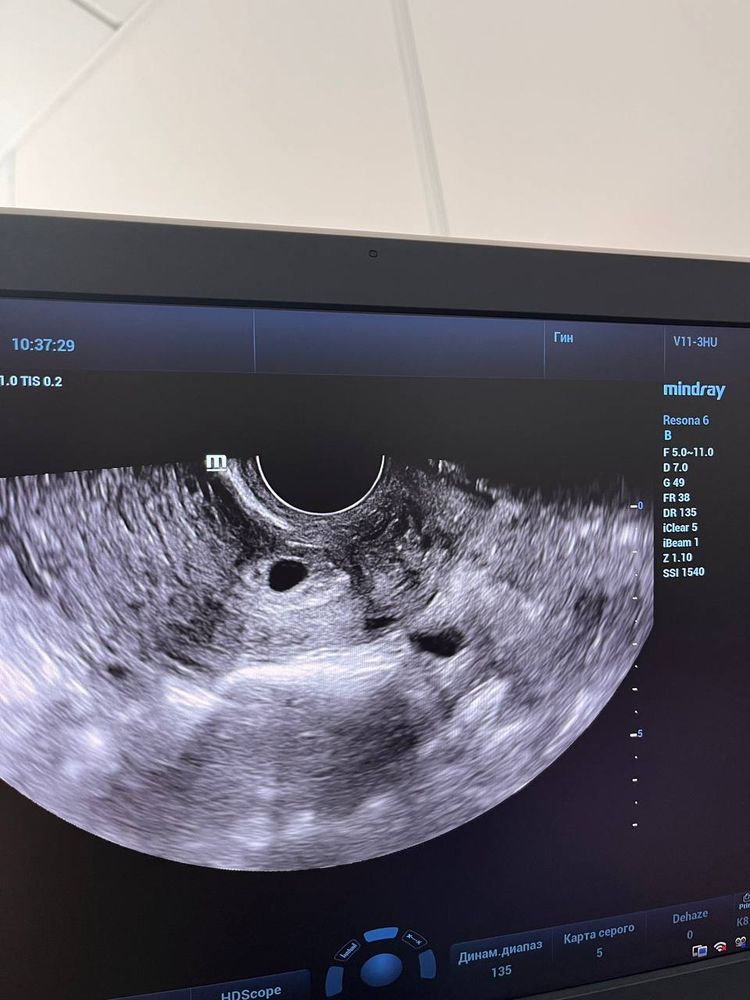

Плохое плодное яйцо